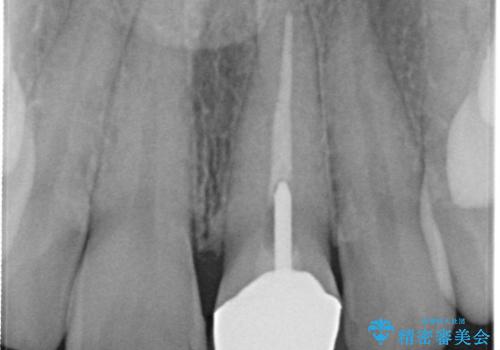

土台も金属だったため、歯がかなり黒く変色していました。

色は完全にとるのが不可能であることをご了承頂いた上で、土台と被せものの治療を行いました。

今回は歯自体が黒くなって歯茎から透けて見えている黒ずみのため、セラミック治療で改善させることは困難だというお話をしました。その上でできる範囲できれいに治療することになりました。

今回のように歯自体が金属イオンで黒く変色すると、被せものをメタルフリーにしても黒ずみをすべて隠すのは困難になります。一方、被せものの金属が見えていることが原因の黒ずみの場合は、セラミック治療できれいになりますので、気になる方は一度ご来院ください。